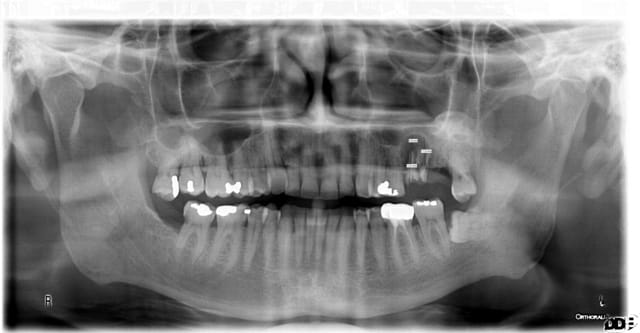

je dois envisager de poser des implants courts pour éviter un soulever de sinus=

26 = 3I cylindro-conique diamètre 6mm enfouit dans 6.5mm d'os D3

27 = 3I pareil en diamètre 5mm (couronne environ 5-6 mm de haut)

le reste de l'oclusion est OK.

Ma question = le gars ayant cassé les racines sous cc de 26-27 par bruxisme à un an d’intervalle je me demande si ça tiendra le choc même si j'envisage 2 couronnes solidarisées

PS= ne vous effrayez pas, la pano date de l'année dernière, depuis soins, extractions et comblements puis délai de cicat...